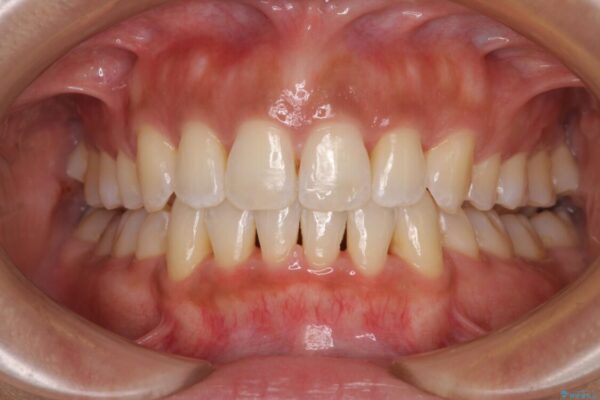

治療後

• 抜歯矯正で唇を閉じやすく 目立たないワイヤー装置 治療後画像

抜歯スペースに前歯を移動させることで歯の突出感が改善され、非常に唇が閉じやすい仕上がりとなりました。